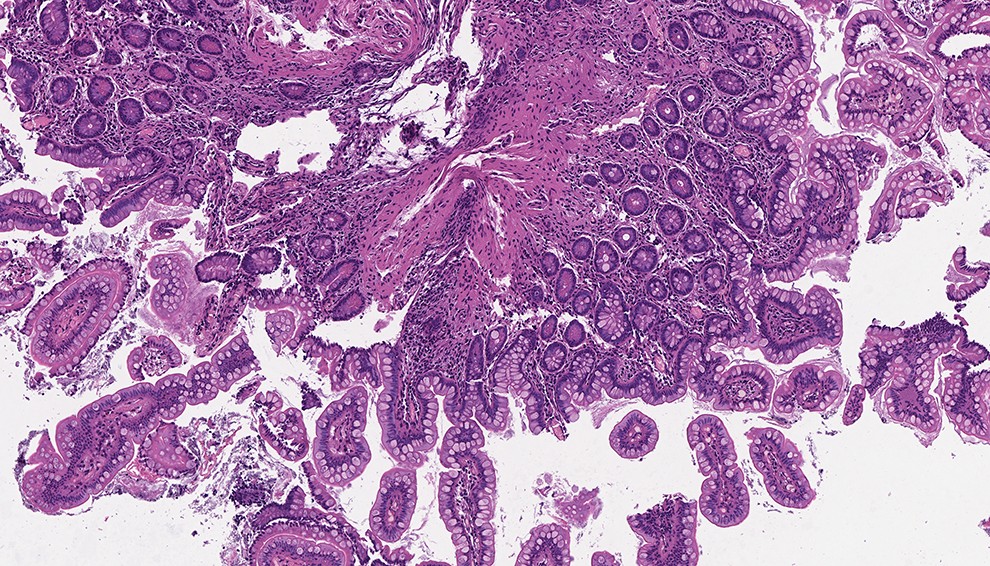

Окончив учебу, Ремез вернулся в Россию, работал менеджером в разных проектах. Сначала они не имели отношения к медицине, но в 2013 году ему предложили работу в проекте по запуску лаборатории Laboratoires De Genie. Она занялась патоморфологическими исследованиями в области диагностики онкологических заболеваний. Такой тип исследований, когда для выявления онкологии срезы тканей окрашиваются химическими веществами гематоксилином и эозином, является обязательным в случае, если врач подозревает наличие раковой опухоли у пациента.